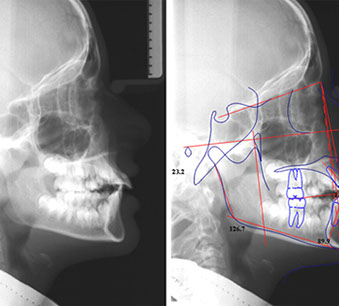

una teleradiografia laterale (che serve per eseguire le misurazioni cefalometriche utili alla formulazione di un piano di trattamento ortodontico)

Con questi esami lo specialista esegue un tracciato cefalometrico, e se necessario inizia un trattamento ortopedico funzionalizzante che utilizza un apparecchio mobile (i bambini lo possono mettere e togliere da soli) con il quale si può guidare la crescita dei denti in posizione corretta, guidare la crescita delle basi ossee e correggere abitudini viziate come succhiare il dito e respirare con la bocca aperta.